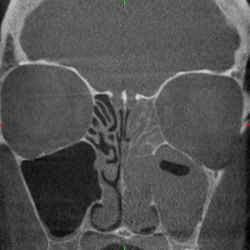

Osteosynthese nach

Mittelgesichtsfraktur